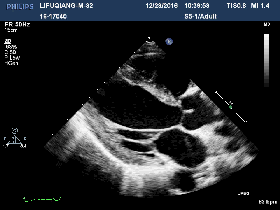

2016-12-20

◆BNP:115pg/ml

◆肌酐: 317umol/L

◆心超:

▶左房左室内径较前相仿

▶左室收缩功能整体减退,LVEF 43%

▶左室舒张功能未见异常E/E`=8

▶左室下壁心尖段见1处条索样回声,随血流甩动,大小约8mm

▶右房右室内径正常,TAPSE 17mm

▶心包腔内未见无回声区